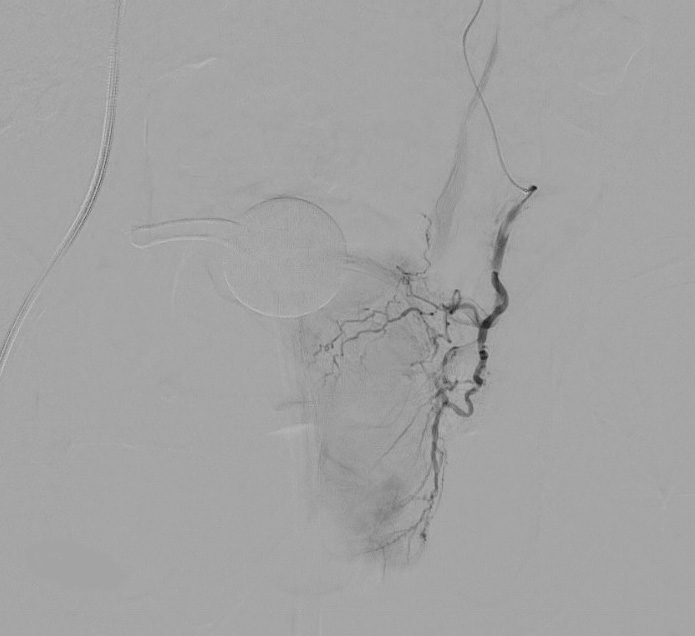

PAE is presented as an alternative to TURP. This treatment is part of a class of procedures called minimally invasive image-guided procedures (MIIPs). The procedure itself shrinks the prostate by treating its blood vessels. It is performed by an interventional radiologist who gains access through a small incision in the upper thigh. Small particles are injected to slow the blood flow to the gland. After PAE, the prostate relaxes and shrinks, resulting in symptom relief for most men in the following weeks and months.